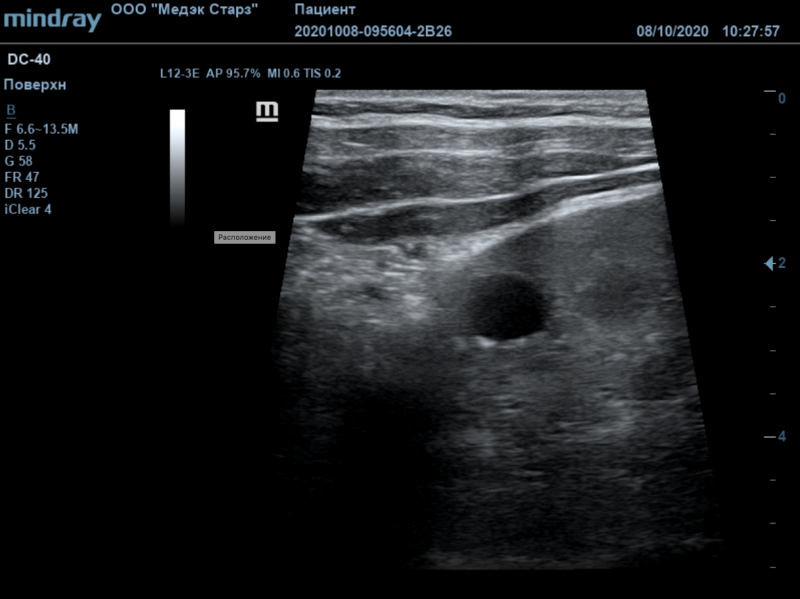

Ультразвуковая система Philips EPIQ CVx предоставляет врачу широкий спектр возможностей для еще более качественной и точной визуализации. Благодаря высокому разрешению дисплея, система обеспечивает максимальную детализацию как в 2D, так и в 3D режимах, а также при доплеровском картировании.

Ультразвуковая система Philips EPIQ CVx предоставляет врачу широкие возможности для еще более качественной и точной визуализации. Благодаря высокому разрешению дисплея, система обеспечивает максимальную детализацию как в 2D, так и в 3D режимах, а также при доплеровском картировании. Технологии Philips позволяют специалистам расположить УЗ-снимок на всей диагонали экрана в режиме реального времени без потери качества.